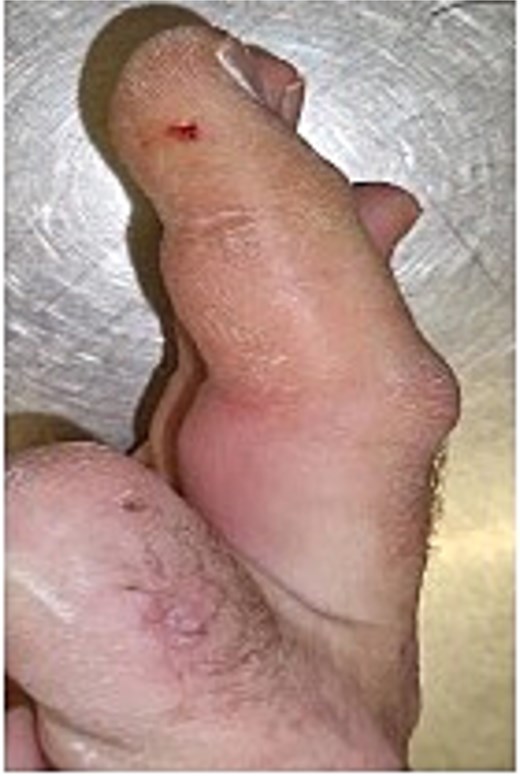

Initial presentation (Fig. 7) with accompanying X-ray (Fig. 8). Final image shows patients digit when he represented 2 months after original insult with a swollen finger and pus exudate (Fig. 9).

Patients three’s digit when he represented 2 months after original insult with a swollen finger in a flexed position and pus exudate.